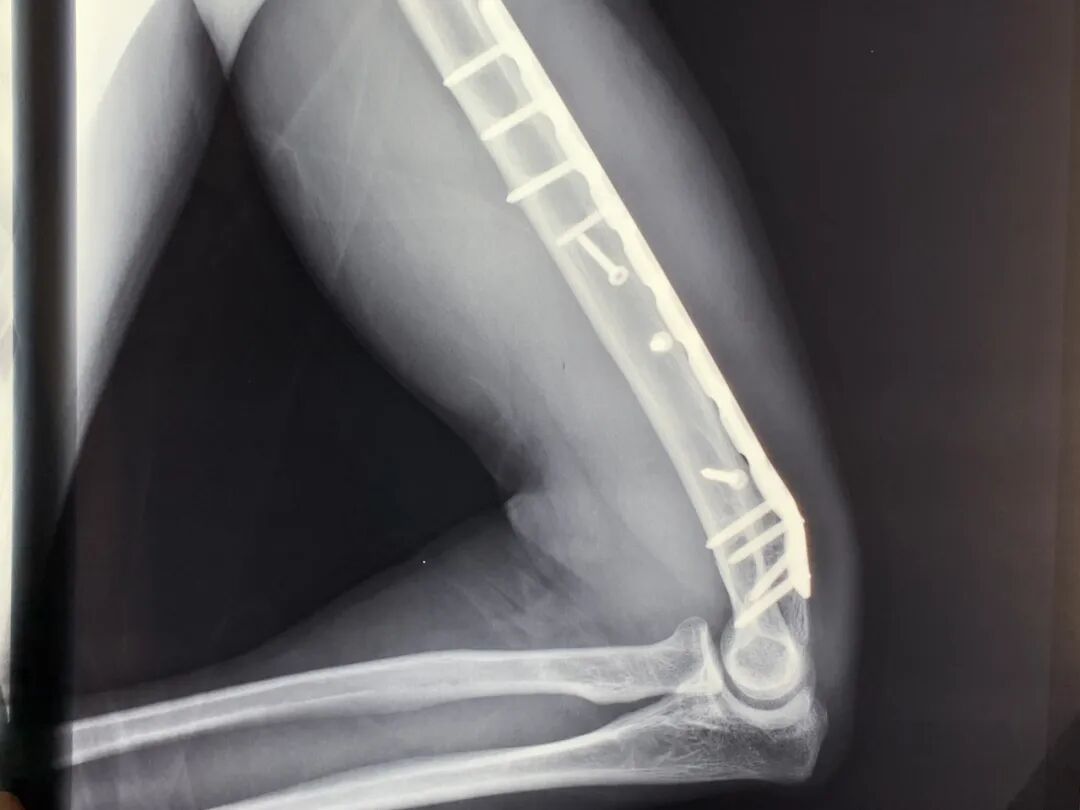

事后检查显示

“肱骨被拧断成了麻花状”